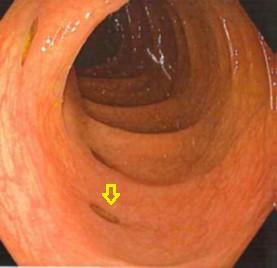

當腸道持續受壓,較薄弱的地方便會形成憩室(黃色箭嘴位置)。